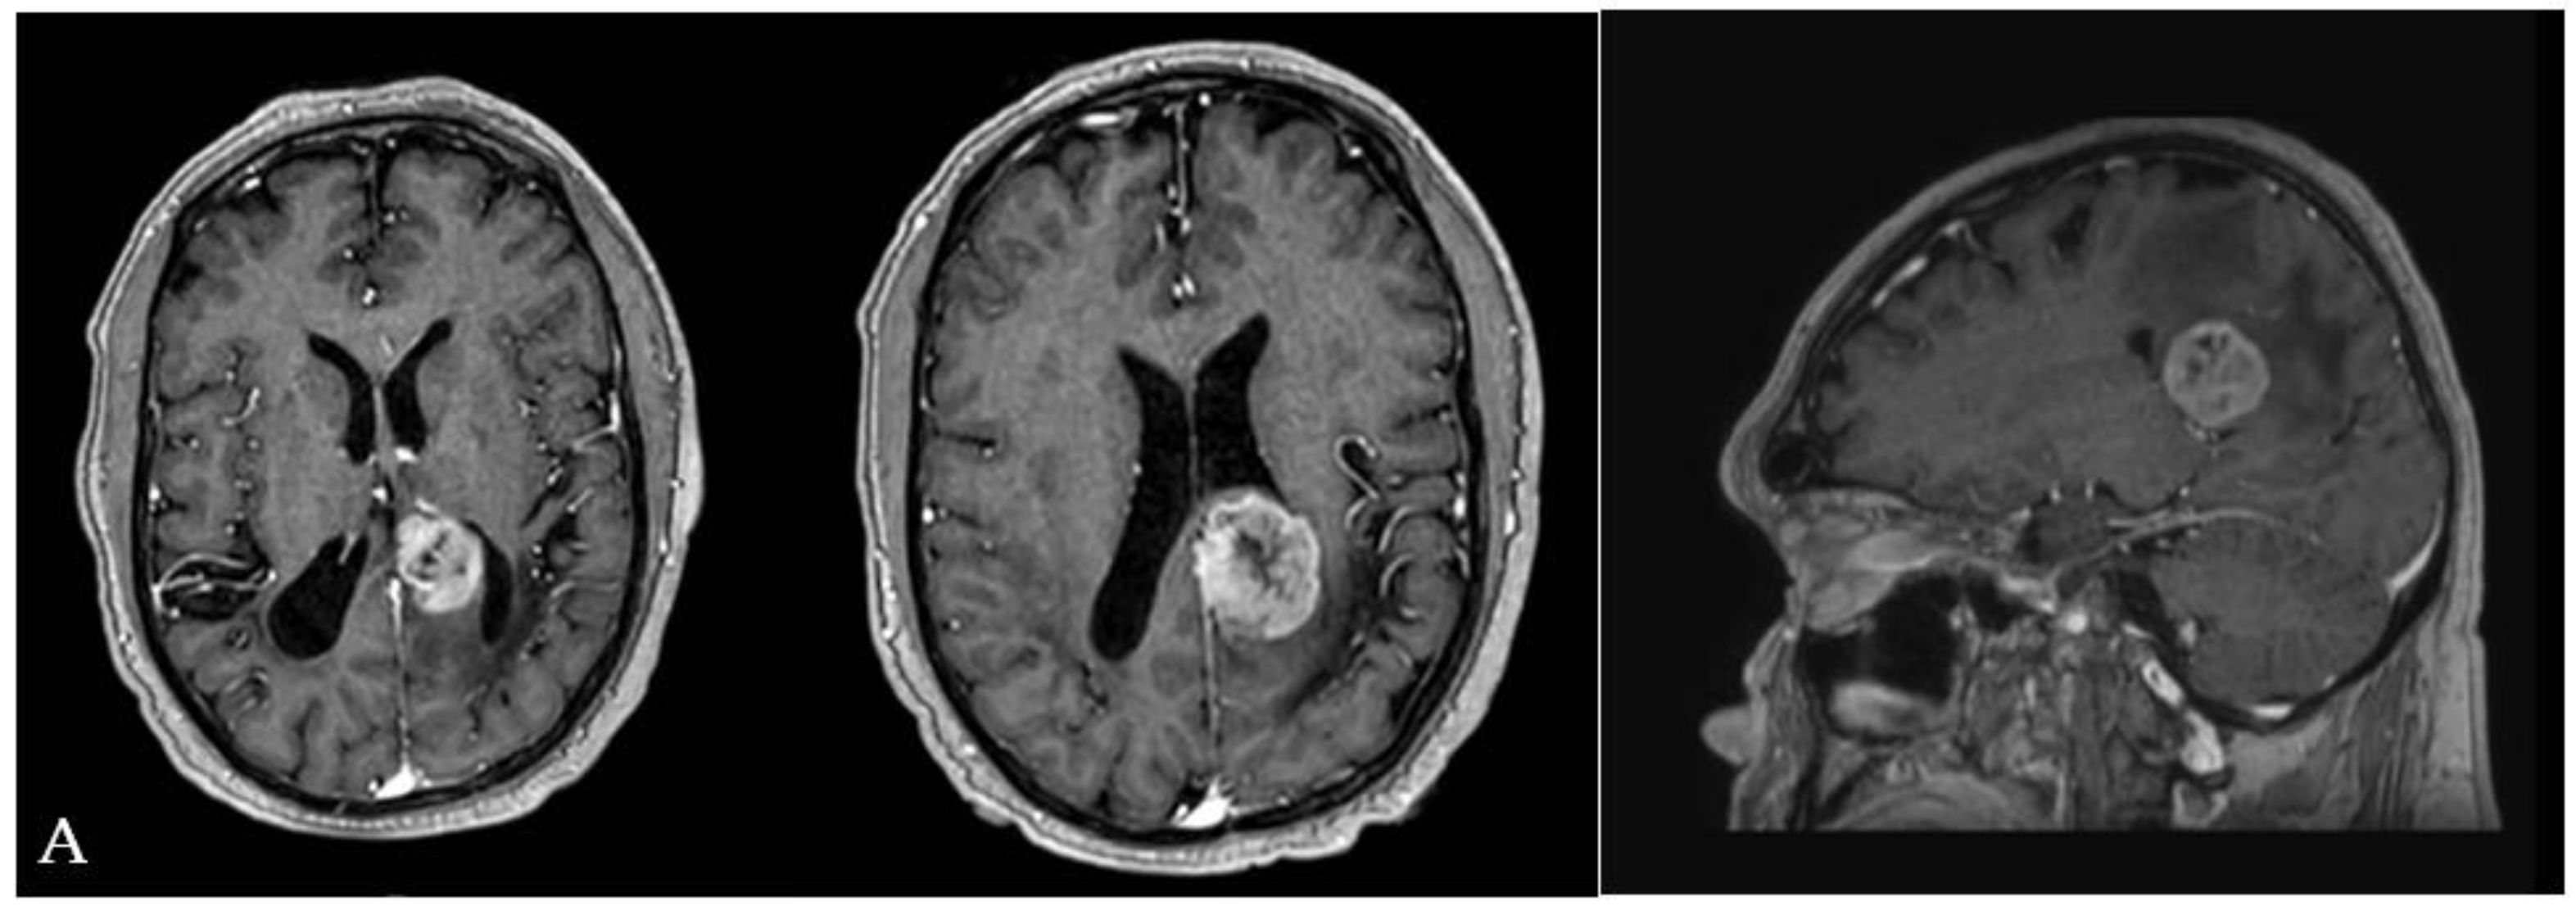

Figure 5. (A) Pre-operative MRI documenting the presence of a lesion partially involving the left atrial cavity of the lateral ventricle. (B) Three-quarter prone position for the IITA. (C) Immediate post-operative MRI (T1 sequence with cm) control documenting the complete resection of the lesion and the rehabilitation of the atrial cavity. (D) Immediate post-operative MRI (T2 sequence). Note the absence of post-surgical brain edema. (E) One month post-operative neuological evaluation and surgical linear incision aspect.

• Illustrative case n.2 (Case n.4 in the table, Figure 5)

A 35-year-old man with a history of melanoma came to our attention because of a drug-resistant headache and aphasia. A brain MRI was performed documenting the presence of a left-sided solid lesion enhancing after the administration of mc partially involving the atrial cavity of the lateral ventricle. The total body CT scan excluded the presence of other metastases. The patient underwent surgical removal through IITA.

Immediately, a post-operative MRI was performed, documenting the complete removal of the lesion. T2 weighted sequences excluded the presence of post-surgical brain edema.

The post-operative course was favorable. His aphasia was remitted, as well as his headache. The patient was discharged on the fifth post-operative day.